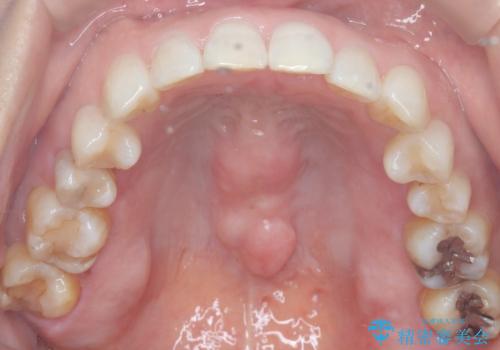

インビザラインで非抜歯矯正|ゴムかけで下顎犬歯の低位を改善し、噛み合わせも最適化

- 患者様は、下顎の犬歯が通常より低い位置にあり、噛み合わせのバランスが崩れていることを気にされて来院されました。診査の結果、抜歯せずに歯をきれいに並べるスペースを確保しながら、**ゴムかけ(顎間ゴム)**を使用して下顎犬歯の高さを適正に調整する方針を立てました。併せて、奥歯の噛み合わせも改善し、全体のバランスを整えることを目標としました。

治療はインビザライン(マウスピース矯正)を使用し、歯列全体を計画的に移動させながら、下顎犬歯の低位をゴムかけによって徐々に引き上げました。患者様にはゴムの装着をしっかり継続していただき、順調に改善が進行。最終的に奥歯の噛み合わせも安定し、全体の咬合バランスが整いました。治療後は「自然な噛み心地になり、見た目も満足」と患者様にも喜んでいただきました。